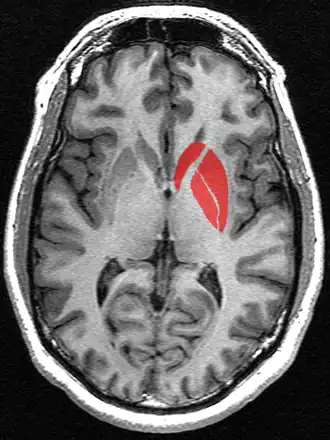

De basale kernen, waar het putamen toe behoort, aangegeven in het paars.

Het putamen[1] is een rondvormige kern in de basis van de grote hersenen, die samen met de nucleus caudatus het corpus striatum vormt. Daarnaast behoort het putamen tot de basale kernen. Het putamen is functioneel verbonden met de substantia nigra en de globus pallidus langs meerdere zenuwbanen. De belangrijkste functie is de regulatie van bewegingen en het beïnvloeden van meerdere soorten leren. De neurotransmitters GABA, acetylcholine en enkefaline worden door het putamen geproduceerd om deze functies te kunnen uitvoeren. Het putamen speelt ook een rol in neurodegeneratieve ziekten, zoals de ziekte van Parkinson.

Samen met de globus pallidus vormt het putamen de nucleus lentiformis.

Het putamen en de nucleus caudatus vormen anatomisch gezien één structuur, het striatum dorsale, dat wordt doorkruist door de capsula interna. Daarnaast vormt het putamen samen met de globus pallidus de nucleus lentiformis. Het putamen is de buitenste structuur die behoort tot de basale kernen, een groep kernen met wijdverspreide verbindingen in de hersenschors, thalamus en hersenstam. Ook de substantia nigra, nucleus accumbens en de nucleus subthalamicus worden tot de basale kernen gerekend.

Het putamen komt in beide hersenhelften voor en is nauw verbonden met drie andere basale kernen. Ten eerste werkt het putamen samen met de nucleus caudatus om input vanuit de hersenschors te ontvangen. De twee structuren vormen zo de "ingang" tot de basale kernen. Ten tweede is het putamen verbonden met de globus pallidus, waaraan het output doorgeeft. Ten derde ontvangt de pars compacta substantiae nigrae input van het putamen.